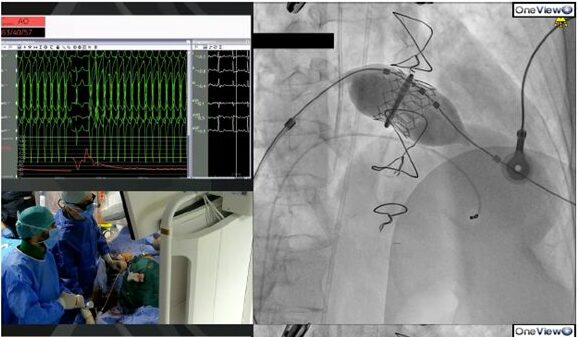

La peculiarità di questo intervento risiede nella combinazione di tre tecniche: il valve in ring, la tecnica lampoon e l’aggiunta di un approccio con puntura transapicale. La procedura ha richiesto un’attenta pianificazione e valutazione delle immagini anatomiche tramite ecografia transofagea e TAC, al fine di prevedere tutte le possibili complicanze.

Uno dei rischi anatomici principali era legato alla potenziale ostruzione del canale di efflusso del cuore a causa dell’impianto della valvola. Per evitare questo problema, è stata eseguita prima dell’impianto della valvola la lacerazione di un lembo valvolare (“lampoon”), creando lo spazio necessario per l’inserimento della protesi senza ostruzioni.

Un altro aspetto tecnico critico era legato all’orientamento dell’anello mitralico in cui si doveva impiantare la protesi rispetto all’asse principale del cuore. Attraverso lo studio con TAC, è stata simulata la teorica posizione della protesi rispetto all’asse dell’anello e misurato l’asse teorico ideale di impianto per ridurre i rischi di malapposizione e malfunzione della protesi.

In base a tale accurato studio si è deciso di eseguire un ulteriore approccio assolutamente innovativo, mediante puntura dell’apice cardiaco, al fine di creare con l’esposizione esterna della guida su cui si doveva impiantare la protesi, l’asse ottimale per l’impianto. La procedura è stata eseguita con successo e alla fine il “foro” dell’apice del cuore è stato perfettamente sigillato con una piccola protesi “a tappo”.